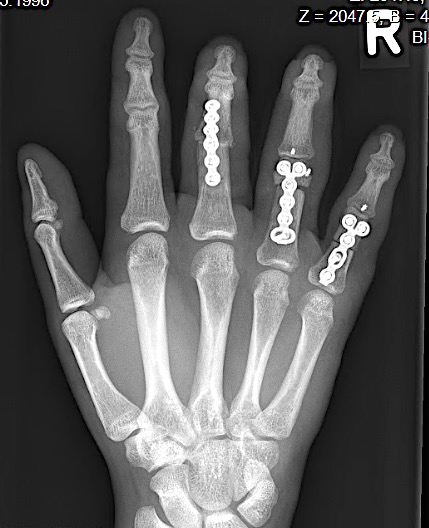

Case 2:

A 20-year-old male suffered a complex multi-digit injury of the right hand requiring revascularization and stabilization of both proximal phalanx and PIP joint fractures (Figs 5 - 8). Multiple plates, including the rotation correction plate from the 1.5 module of the VA Locking Hand System were used for fixation. The Variable Angle Locking system is ideal when only two screws, either proximal or distal, are able to be inserted due to space limitation.

One major advantage of variable angle technology in very distal phalangeal fractures is the ability to be extremely flexible with a wide range of fixation options. Freedom of implant placement assists early mobilization, vital in these complex fractures with associated soft-tissue trauma.